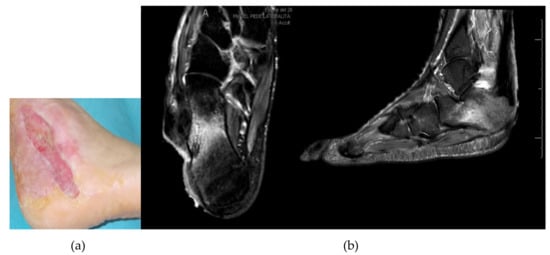

3.1. Calcaneal Lesions

3.3. Lesions Involving Distal Tarsus & Talus